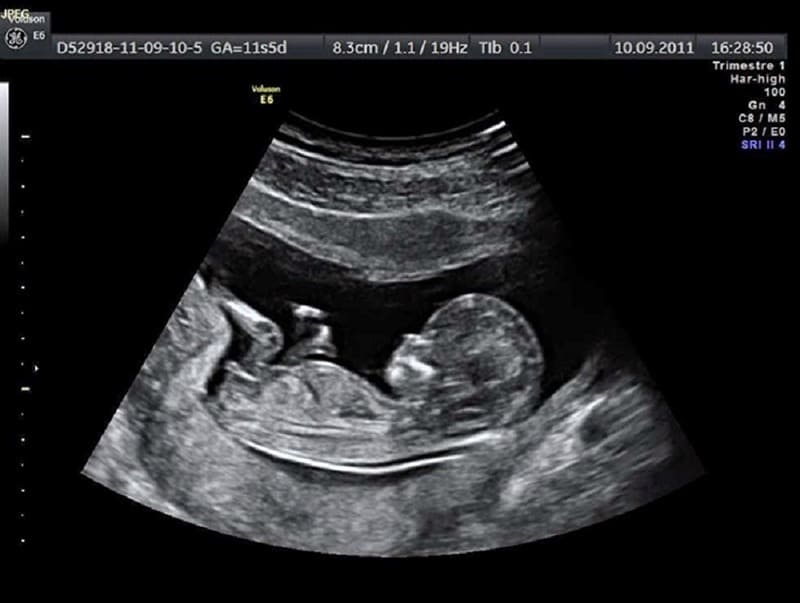

- Từ tuần 12–14: có thể quan sát và đo sơ bộ, nhưng chưa chính xác tuyệt đối.